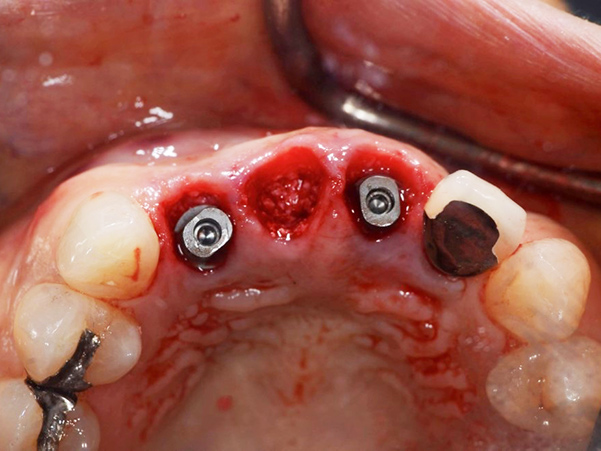

1次手術時の流れ

④サージガイドを使用したインプラント体の埋入

⑤インプラント体を埋入した状態

⑥仮歯を製作していく段階

⑦仮歯を装着した状態

埋入したばかりのインプラント体に負担がかからないように、下の歯と当たらないような形と噛み合わせになるよう調整しています。